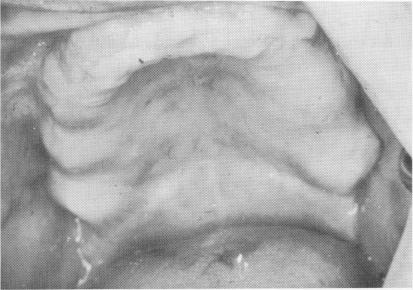

The soft tissue covering the edentulous maxilla was pierced from tuberosity to tuberosity along the crest of the ridge with a sharp scalpel (Fig. 11-167). The tissue was retracted with a periosteal elevator to expose the buccal and labial aspects of the ridge and part of the palatal portion. A groove was created along the center of the ridge from one side of the arch to the other with a No. 700L fissure bur. Its depth was never more than 3 mm. (Fig. 11-168).

Fig. 11-168. Underlying alveolar crest was exposed and a 2- to 3-mm. continuous groove was made. (From Linkow, L. I., and Weiss, J. L.: The endosseous blade: a progress report, Prom. Dent., No. 5, 1969.)

3 Underlying maxillary alveolar crest exposed and continuous groove made